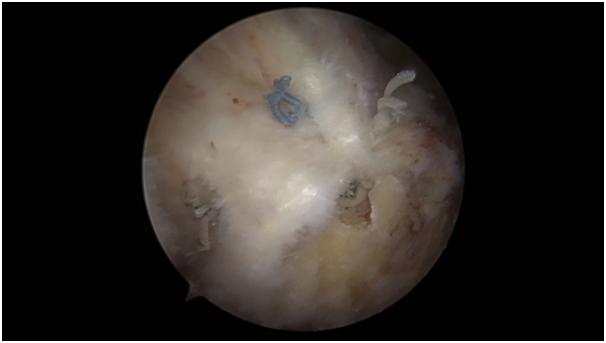

Είναι μια ελάχιστα-επεμβατική τεχνική οριστικής θεραπείας της εμμένουσας ασβεστοποιού τενοντίτιδας ώμου, την οποία έχει αναπτύξει ο Επίκουρος Καθηγητής, Δρ. Μαλαχιάς. Τα κλινικά αποτελέσματα της τεχνικής αυτής είναι πολύ ικανοποιητικά, όπως έδειξε κλινική μελέτη του Δρ. Μαλαχιά, η οποία δημοσιεύθηκε το 2020, στο διεθνές περιοδικό Journal of Orthopaedics (https://www.ncbi.nlm.nih.gov/pmc/articles/PMC7067993/). Η τεχνική αναρρόφησης διπλής βελόνης είναι ανώδυνη και πραγματοποιείται στο ιατρείο, αφού προηγηθεί μια απλή ένεση τοπικής αναισθησίας στον ώμο. Εν συνεχεία, υπό άσηπτες συνθήκες και υπό συνεχή καθοδήγηση υπερήχου, στην οθόνη του οποίου καταγράφουμε τη θέση της ασβέστωσης, του τένοντα και του θυλάκου, εισάγουμε 2 βελόνες εντός της ασβέστωσης. Οι βελόνες αυτές είναι επίσης ορατές στην οθόνη του υπερήχου. Με αυτόν τον τρόπο επιβεβαιώνουμε ότι οι βελόνες στόχευσαν ορθώς και εισήχθησαν ακριβώς εκεί που επιθυμούμε, δηλαδή στο κέντρο της ασβέστωσης. Μέσα από τις βελόνες αυτές χορηγούμε φυσιολογικό ορό, ξεπλένοντας και μαλακώνοντας την ασβέστωση. Κατόπιν, αναρροφούμε την μαλακωμένη ασβέστωση με μια σήραγγα, τραβώντας την εναλλάξ από κάθε βελόνα. Αυτό το κάνουμε μέχρι να αποδιοργανωθεί η ασβέστωση στην οθόνη του υπερήχου και να δούμε τα λευκά ίχνη (κόκκινο βέλος στη φώτο) της αναρροφηθείσας ασβέστωσης μέσα στην σύριγγα.

Ναι! Στις περισσότερες περιπτώσεις, η τεχνική αναρρόφησης διπλής βελόνης (double needle barbotage) - υπό καθοδήγηση υπερήχου – αποδιοργανώνει την ασβέστωση, σε βαθμό τέτοιο που, εν συνεχεία, κινητοποιείται ο ίδιος ο οργανισμός μας και και «τρώει» το υπόλοιπο της ασβέστωσης, εξαφανίζοντάς την.